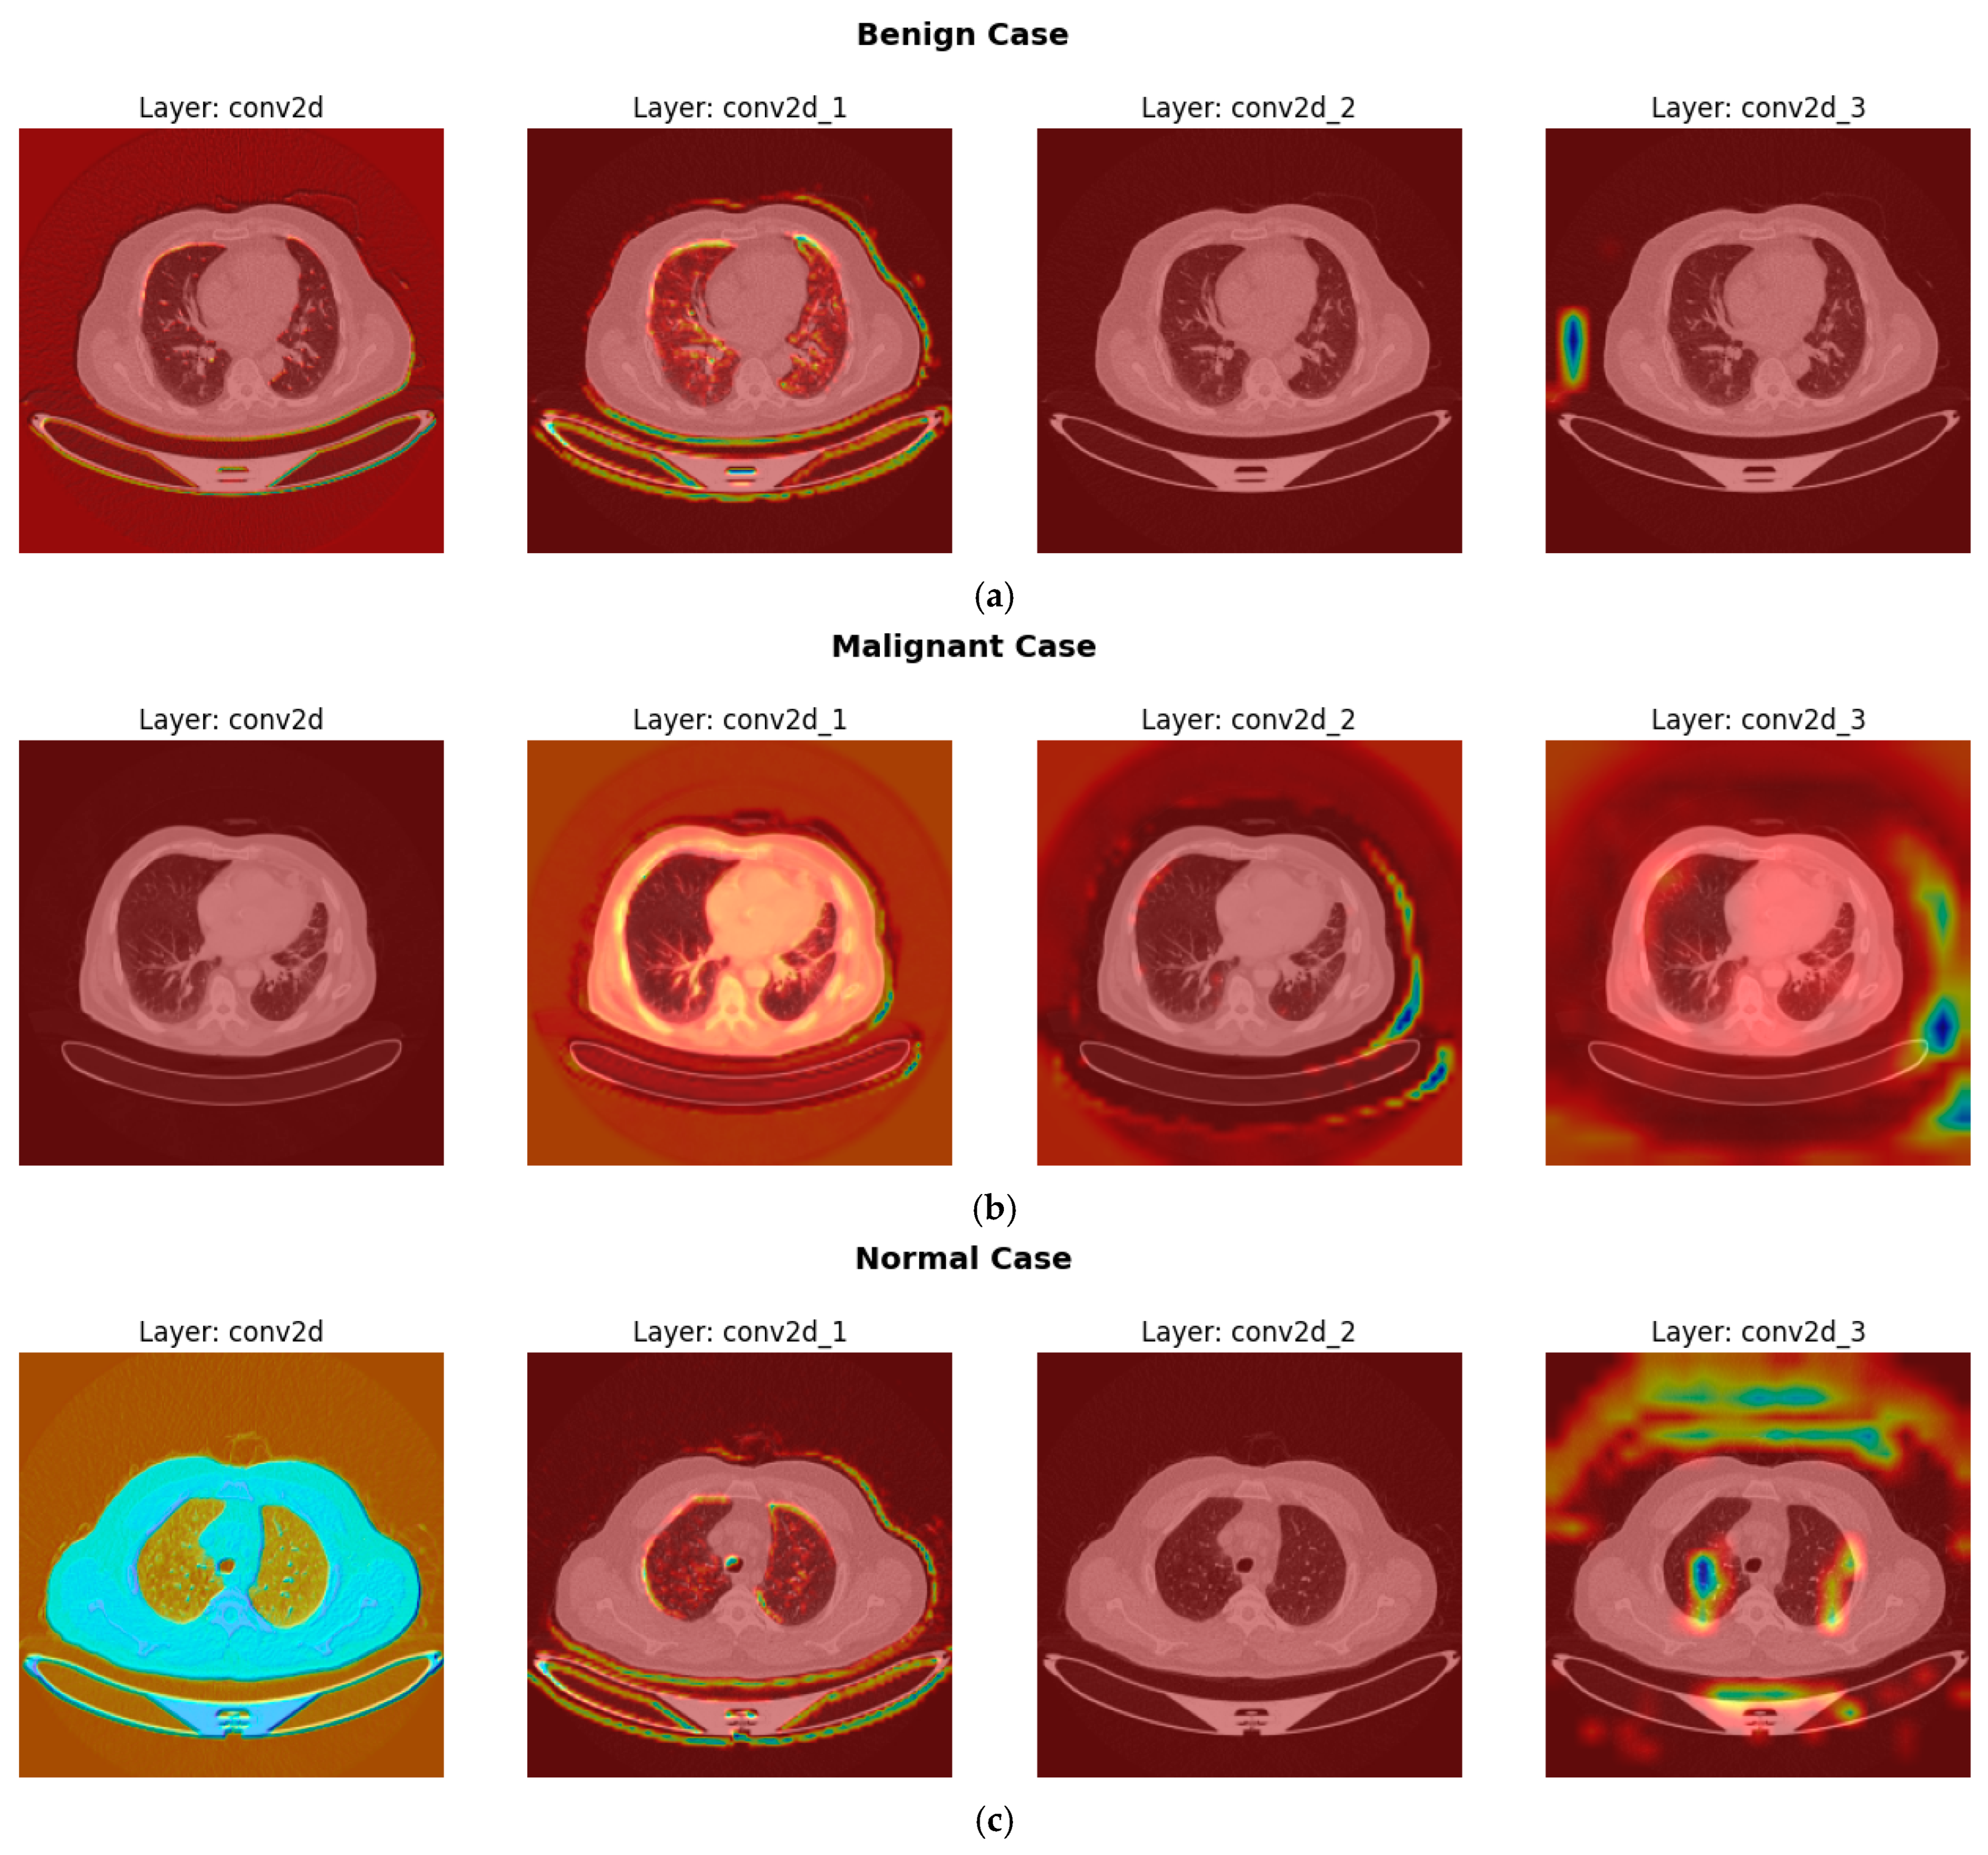

- To enhance interpretability and clinical trust, explainability techniques such as Gradient-weighted Class Activation Mapping (Grad-CAM) are utilized to visualize critical diagnostic regions within CT images that influence the model’s predictions.

3.2.4. Explainable Artificial Intelligence (XAI) Techniques

- Compute Gradients: Calculate the gradients of the target class score with respect to the feature map of a specific convolutional layer, as shown in Equation (13).where is the activation at spatial location (i,j) in the k-th feature map.

- Global Average Pooling (GAP) for Weights: Compute the neuron importance weights for each feature map k as shown in Equation (14). This is achieved by performing a global average pool of the gradients calculated in step 1.where Z is the total number of spatial locations (i.e., ), these weights represent the “importance” of feature map k for the target class c.

- Weighted Sum of Feature Maps: Compute the ReLU-activated weighted sum of the feature maps using the calculated weights . Produces the raw Grad-CAM heatmap as illustrated in Equation (15).The ReLU is applied because we are typically interested in features that positively influence the class score.

- Upsampling and Superimposition: The resulting heatmap is typically low-resolution (same as the feature map). It is then upsampled to the original input image size and superimposed onto the input image to visualize the regions of interest that most influenced the CNN’s decision for the target class. These visualizations appear as “heatmaps.”

4.6. Interpretation of CNN Decisions Using Grad-CAM Heatmaps